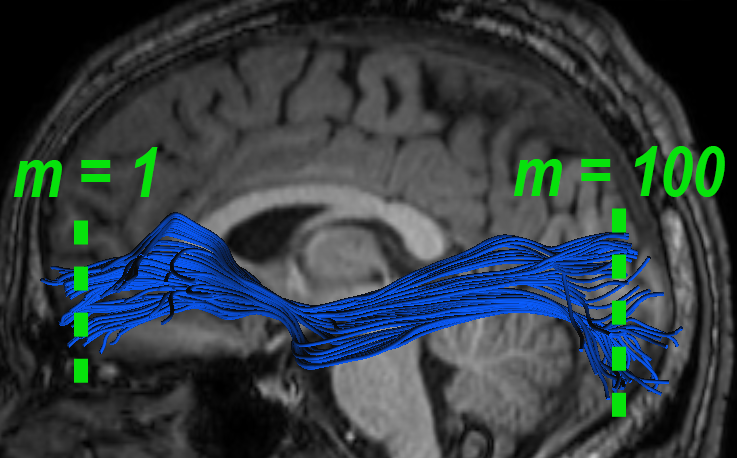

Experiments also showed significant FFDD longitudinal changes between mid-season and post-season scans in some football players. Fig. 7 presents mid- and post-season MD-FFDD profiles comparison of the left IFOF of one of the players, showing increased irregularities over time at the occipital part of the tract. Fig. 8 presents a similar MD-FFDD longitudinal analysis of the FMT of a different player, showing increased irregularities at the central part of the tract.

| Mid vs. Post | Mid-season | Post-season | ||

|---|---|---|---|---|

![]() |

|

STDs |